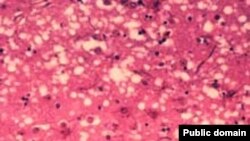

Суд оправдал врачей, которым инкриминировалось массовое заражение болезнью Кройтцфельдта-Якоба («коровьим бешенством»), жертвами которого стали 117 детей. В 1980-е годы прошлого века пострадавшие получали инъекции гормона роста, который в извлекался из трупного материала. Большинству обвиняемых больше 80 лет. Cуд счел недостаточно убедительными аргументы обвинения.

В 1984 году появились первые сообщения о возможной связи между инъекциями гормона роста и «коровьим бешенством». В это же время в ряде развитых стран такие инъекции были запрещены, и карликовость стали лечить синтетическим препаратом. Однако во Франции однозначный запрет не был принят, хотя медиков предупредили об опасности инъекций.

Через 20 лет сотрудникам лабораторий Института Луи Пастера, врачам и чиновникам Министерства здравоохранения были предъявлены обвинения в грубом нарушении техники безопасности, в частности – в использовании при приготовлении препарата тканей людей, скончавшихся от нейродегенеративных и инфекционных заболеваний.